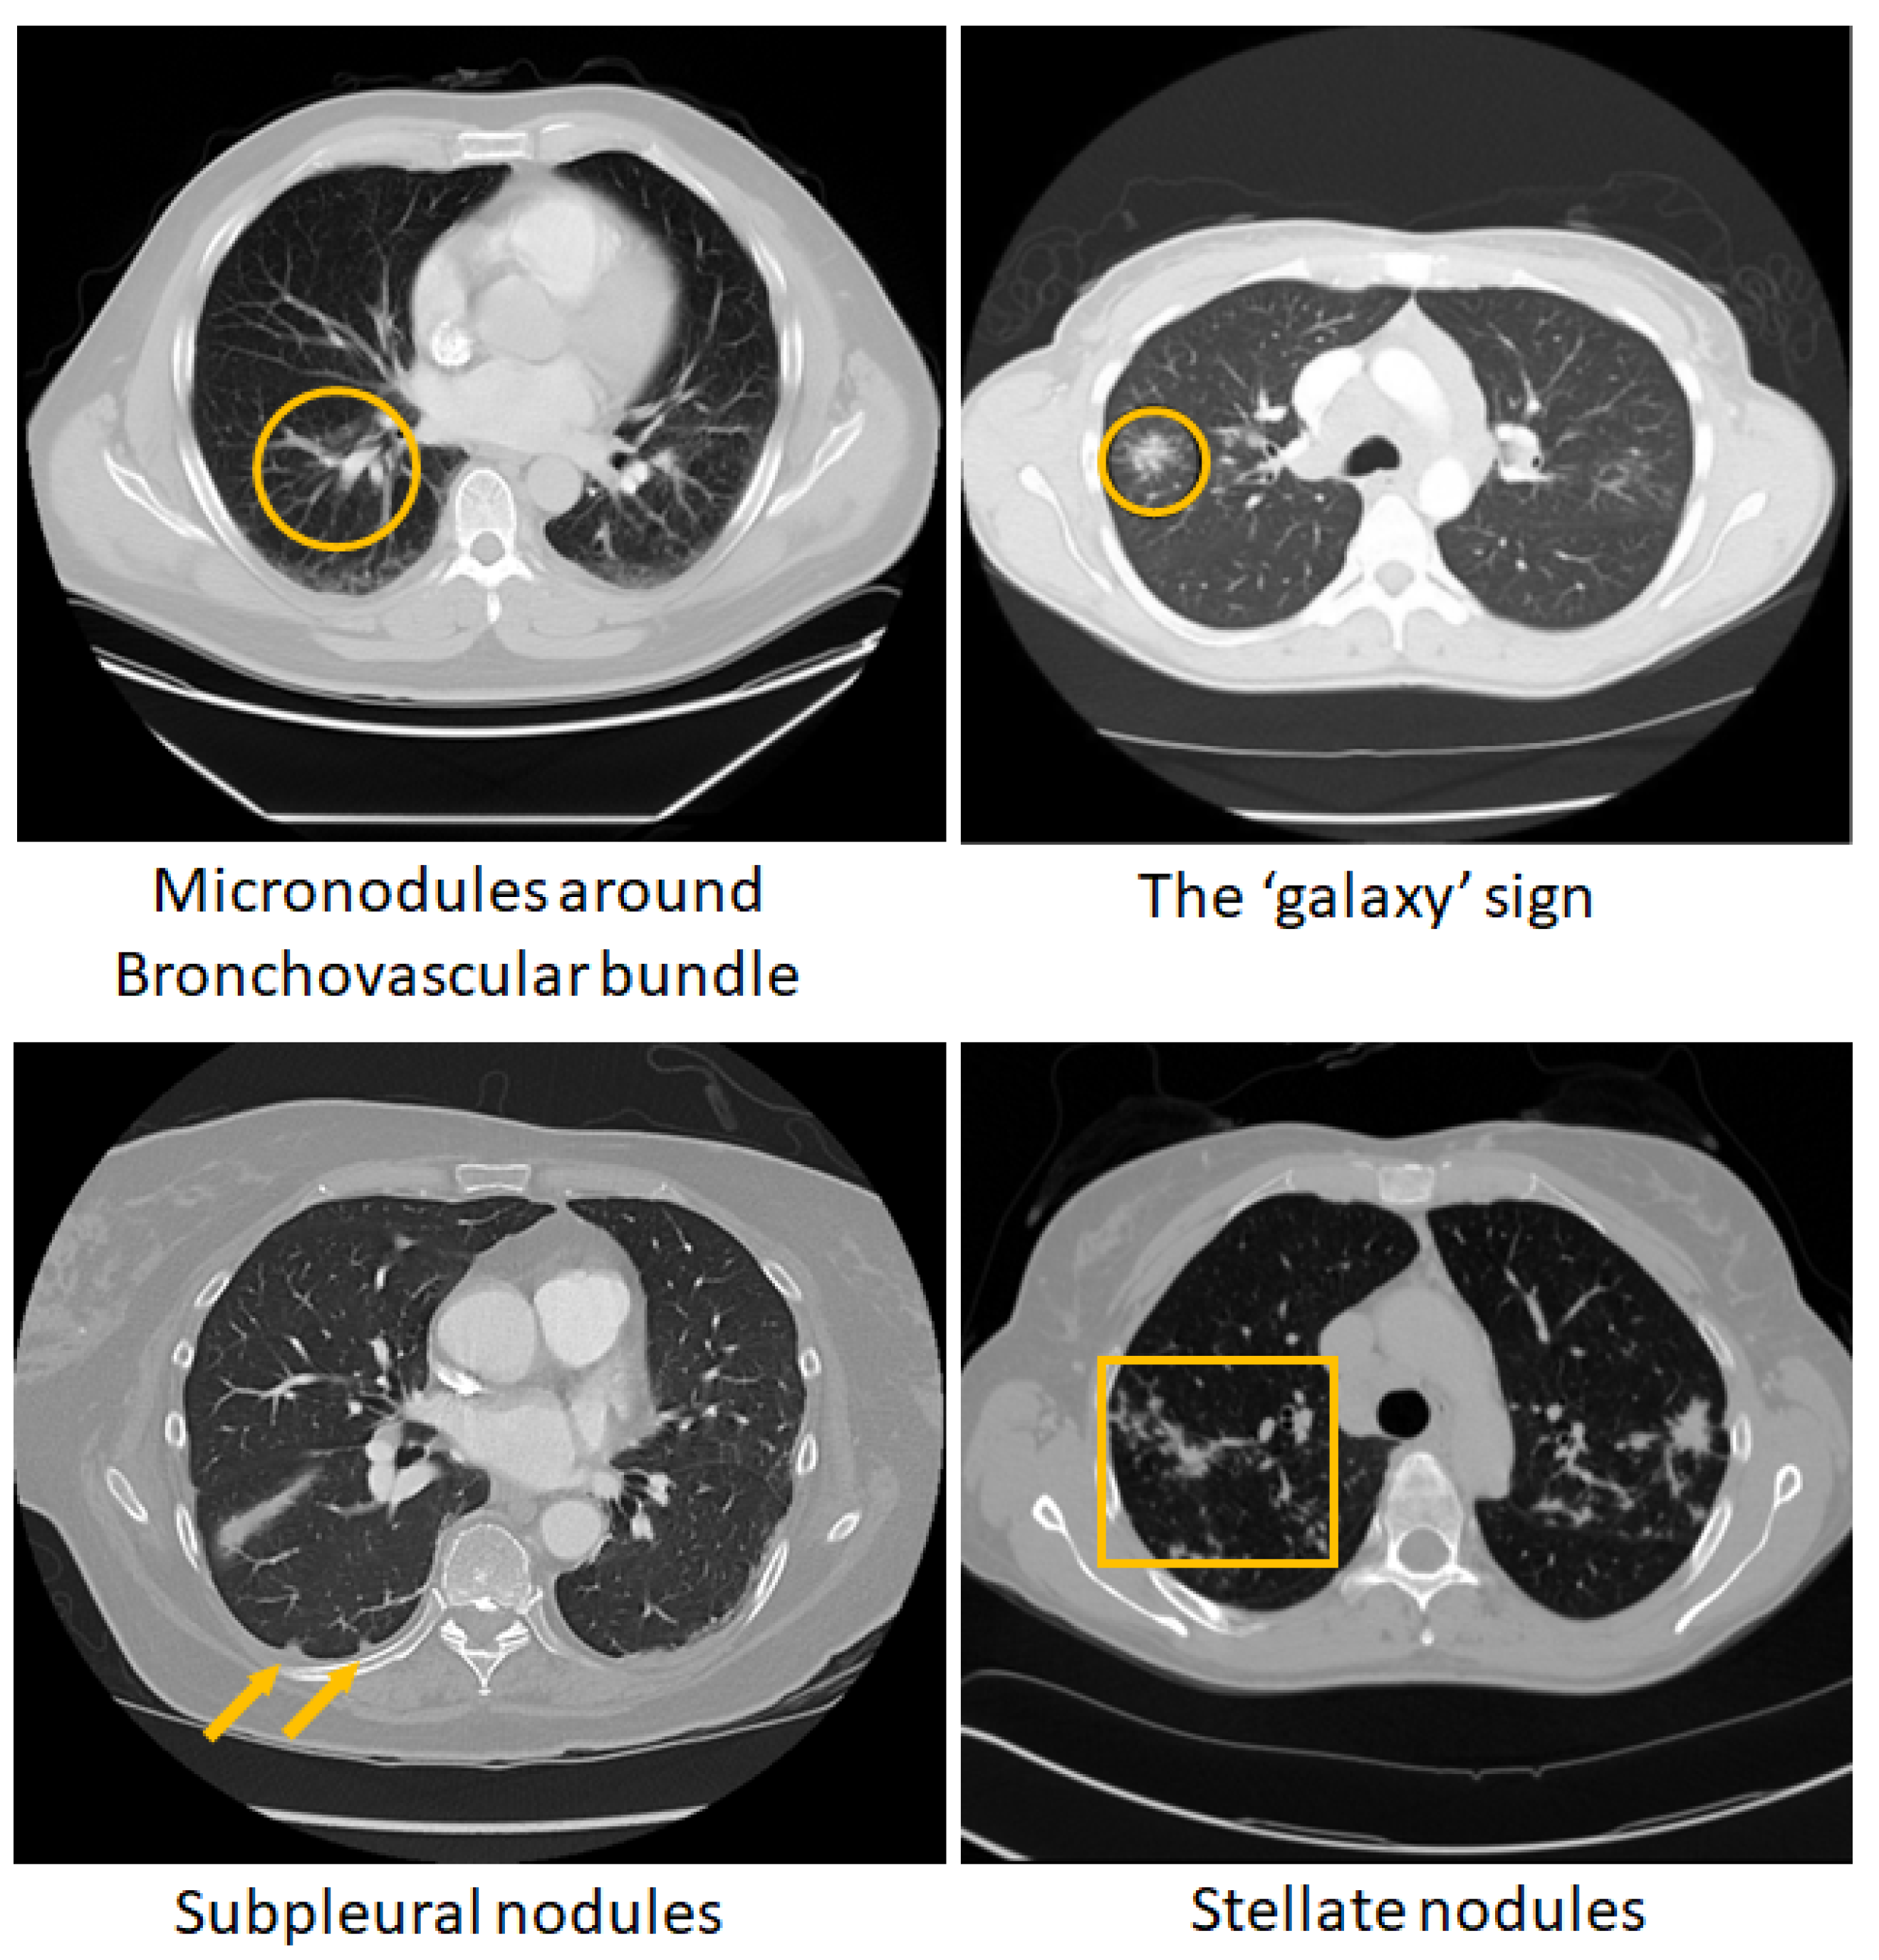

- Tana, C.; Donatiello, I.; Coppola, M.G.; Ricci, F.; Maccarone, M.T.; Ciarambino, T.; Cipollone, F.; Giamberardino, M.A. CT Findings in Pulmonary and Abdominal Sarcoidosis. Implications for Diagnosis and Classification. J Clin Med. 2020, 9, 3028. [Google Scholar] [CrossRef] [PubMed]

- Nakatsu, M.; Hatabu, H.; Morikawa, K.; Uematsu, H.; Ohno, Y.; Nishimura, K.; Nagai, S.; Izumi, T.; Konishi, J.; Itoh, H. Large coalescent parenchymal nodules in pulmonary sarcoidosis: “sarcoid galaxy” sign. AJR. American journal of roentgenology 2002, 178, 1389–1393. [Google Scholar] [CrossRef] [PubMed]

- Koide, T.; Saraya, T.; Tsukahara, Y.; Bonella, F.; Börner, E.; Ishida, M.; Ogawa, Y.; Hirukawa, I.; Oda, M.; Shimoda, M.; others. Clinical significance of the “galaxy sign” in patients with pulmonary sarcoidosis in a Japanese single-center cohort. Sarcoidosis Vasc Diffuse Lung Dis. 2016, 33, 247–252. [Google Scholar]

- Kuhlman, J.E.; Fishman, E.K.; Hamper, U.M.; Knowles, M.; Siegelman, S.S. The computed tomographic spectrum of thoracic sarcoidosis. Radio Graphics 1989, 9, 449–466. [Google Scholar] [CrossRef]

- Kumazoe, H.; Matsunaga, K.; Nagata, N.; Komori, M.; Wakamatsu, K.; Kajiki, A.; Nakazono, T.; Kudo, S. “Reversed halo sign" of high-resolution computed tomography in pulmonary sarcoidosis. J Thorac Imaging 2009, 24, 66–68. [Google Scholar] [CrossRef]